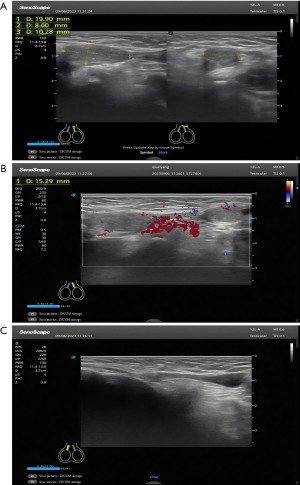

In August 2023, a boy aged 9 months and 19 days, who was the younger brother of case 1, was admitted to our department. Physical examination revealed no testicular mass in the right scrotum or inguinal area. Instead, a testicular-like tissue was found in the left scrotum, and a non-tender mass was palpated in the left inguinal area (Figure 3A). The left testis was normal in size, approximately 12×6×14 mm3, with a smooth surface and uniform echogenicity. The epididymis was normally present bilaterally. A testicular-like echo was observed in the left lower inguinal segment, approximately 20×8×10 mm3. CDFI revealed no abnormal blood flow (Figure 3B), but did reveal a mass in the left inguinal region with intestinal echoes. Ultrasound examination revealed an empty right scrotum with no testicular echo in the right scrotum and groin area (Figure 3C). The preoperative clinical diagnoses were right cryptorchidism and left indirect inguinal hernia.